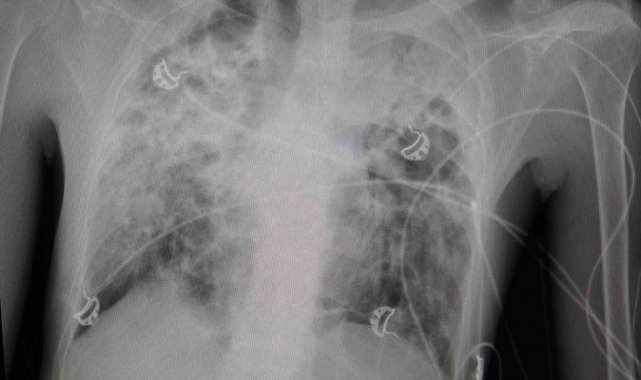

Göğüs Cerrahisi Uzmanı Prof. Dr. Ahmet Erdal Taşçı, akciğer nakli bekleyen hastanın yıllardır bronşektazi hastalığıyla mücadele ettiğini belirterek, "Hastamızın yaşaması için tek çare nakildi. Nakil başarılı geçti. Bu operasyon, bizim ekibimiz için teknik anlamda standart bir akciğer nakliydi. Ancak dikkat çeken nokta, aynı anda hastanemizde bir karaciğer nakli operasyonunun da gerçekleştirilmiş olmasıydı. Aynı bağışçının organları, iki ayrı hastaya; biri akciğer, diğeri karaciğer olarak nakledildi. Bu vesileyle bağışçımıza Allah'tan rahmet, yakınlarına da sabır diliyoruz. Böylesine acılı bir anda başkasının hayatına dokunabilmek, örnek bir davranış" dedi.

"Organ nakli, bir ülkenin sağlık sisteminin ne kadar gelişmiş olduğunu gösteren önemli bir göstergedir." diyen Taşçı, "Ameliyatı gerçekleştirilen hastamız, yoğun bakımda uyanık ve solunum desteğiyle izleniyor. Kısa sürede yeni akciğerleriyle nefes alması bekleniyor" diye konuştu. Taşçı, "Türkiye'de özellikle kadavra donör organ bağışlarının artması büyük önem taşıyor. Herkesin bir gün kendisinin veya sevdiklerinin de bu ihtiyaca düşebileceğini düşünerek, organ bağışı konusunda daha duyarlı ve bilinçli hareket etmesi gerekiyor. Ülkemizde Sağlık Bakanlığı'nın bu alandaki organizasyonu ve altyapısı gerçekten çok iyi seviyede. Bu anlamda emeği geçen herkese teşekkür ediyoruz" ifadelerini kullandı.